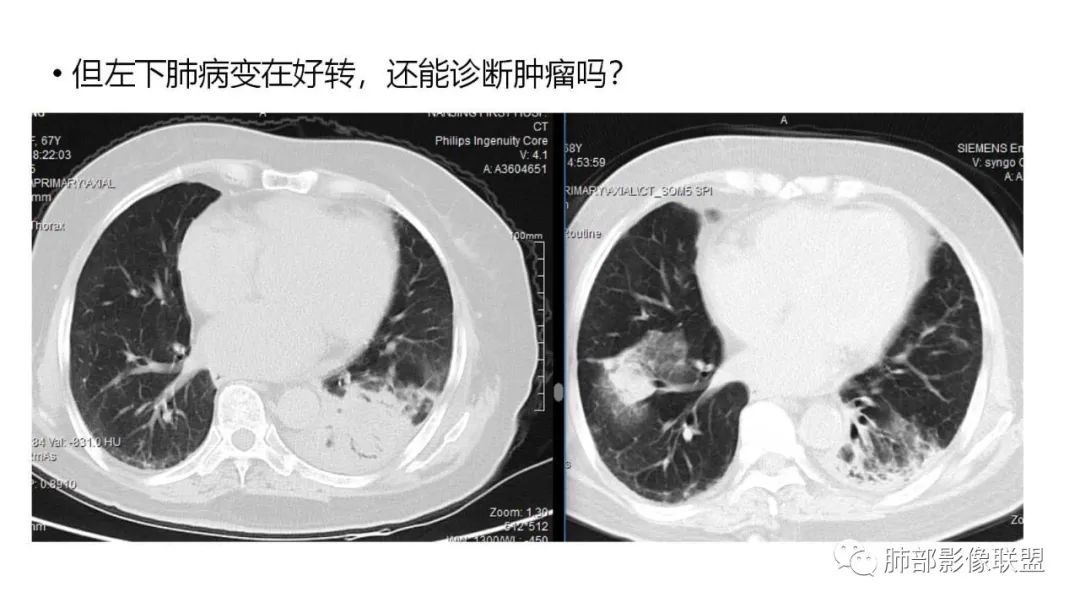

9.粘液腺癌的变化规律:结节缓慢发展而来,向周围播散形成斑片后可快速进展,有时支气管镜后或粘液排出后局部可形成好转的假象。病灶可沿肺泡和支气管播散。

4.回到本例,左下肺病变两次好转,均未经过肿瘤治疗,第一次是支气管镜后,第二次是当其他病变都在进展的情况下,左下肺病变范围反而缩小趋于浅淡。